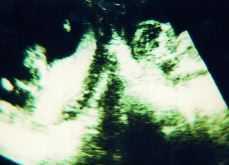

En el curso de su cuarta gestación, en la ecografía realizada a las 18 semanas de amenorrea se estableció el diagnóstico de sospecha de gestación gemelar heterotópica, con un feto en localización intrauterina y otro en un posible cuerno uterino rudimentario (Fig. 1). Este diagnóstico se confirmó mediante RMN, que además aportó el dato de la inexistencia de comunicación entre ambas cavidades (Fig. 2).

Figura 1. Ecografía realizada a las 18 semanas. Diagnóstico de sospecha.